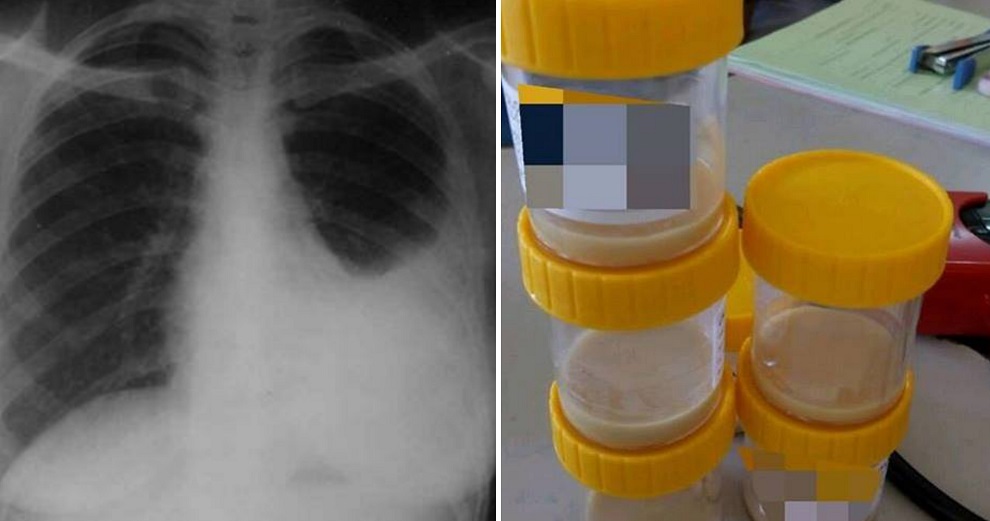

“The amount of oxygen in his body was also very low at just 75 per cent. Ali was immediately given oxygen via face mask. His body was also supported so he could be upright and was given fluids intravenously. We then called the radiologist to conduct an X-ray on him.”

“The X-ray looked similar to the photo below. This isn’t Ali’s X-ray, but a similar picture I found on Google.”

Ali’s X-ray showed that his left lung was filled with fluid. Upon discovering this, Dr Syamirulah decided to drain the fluid from his lung as quickly as possible, since it was building up a lot of pressure. Ali was essentially drowning.

“When I inserted the needle in his chest, a thick yellow-white liquid began to come out. That’s when I realised it was pus.”

He managed to drain 200 millilitres of pus, yet there was no sign of it stopping. So, the doctor decided to use a chest tube in an effort to remove as much pus as possible.

When he finished the procedure, Dr Syamirulah managed to drain nearly one litre of pus from Ali’s lung.

Source: Facebook